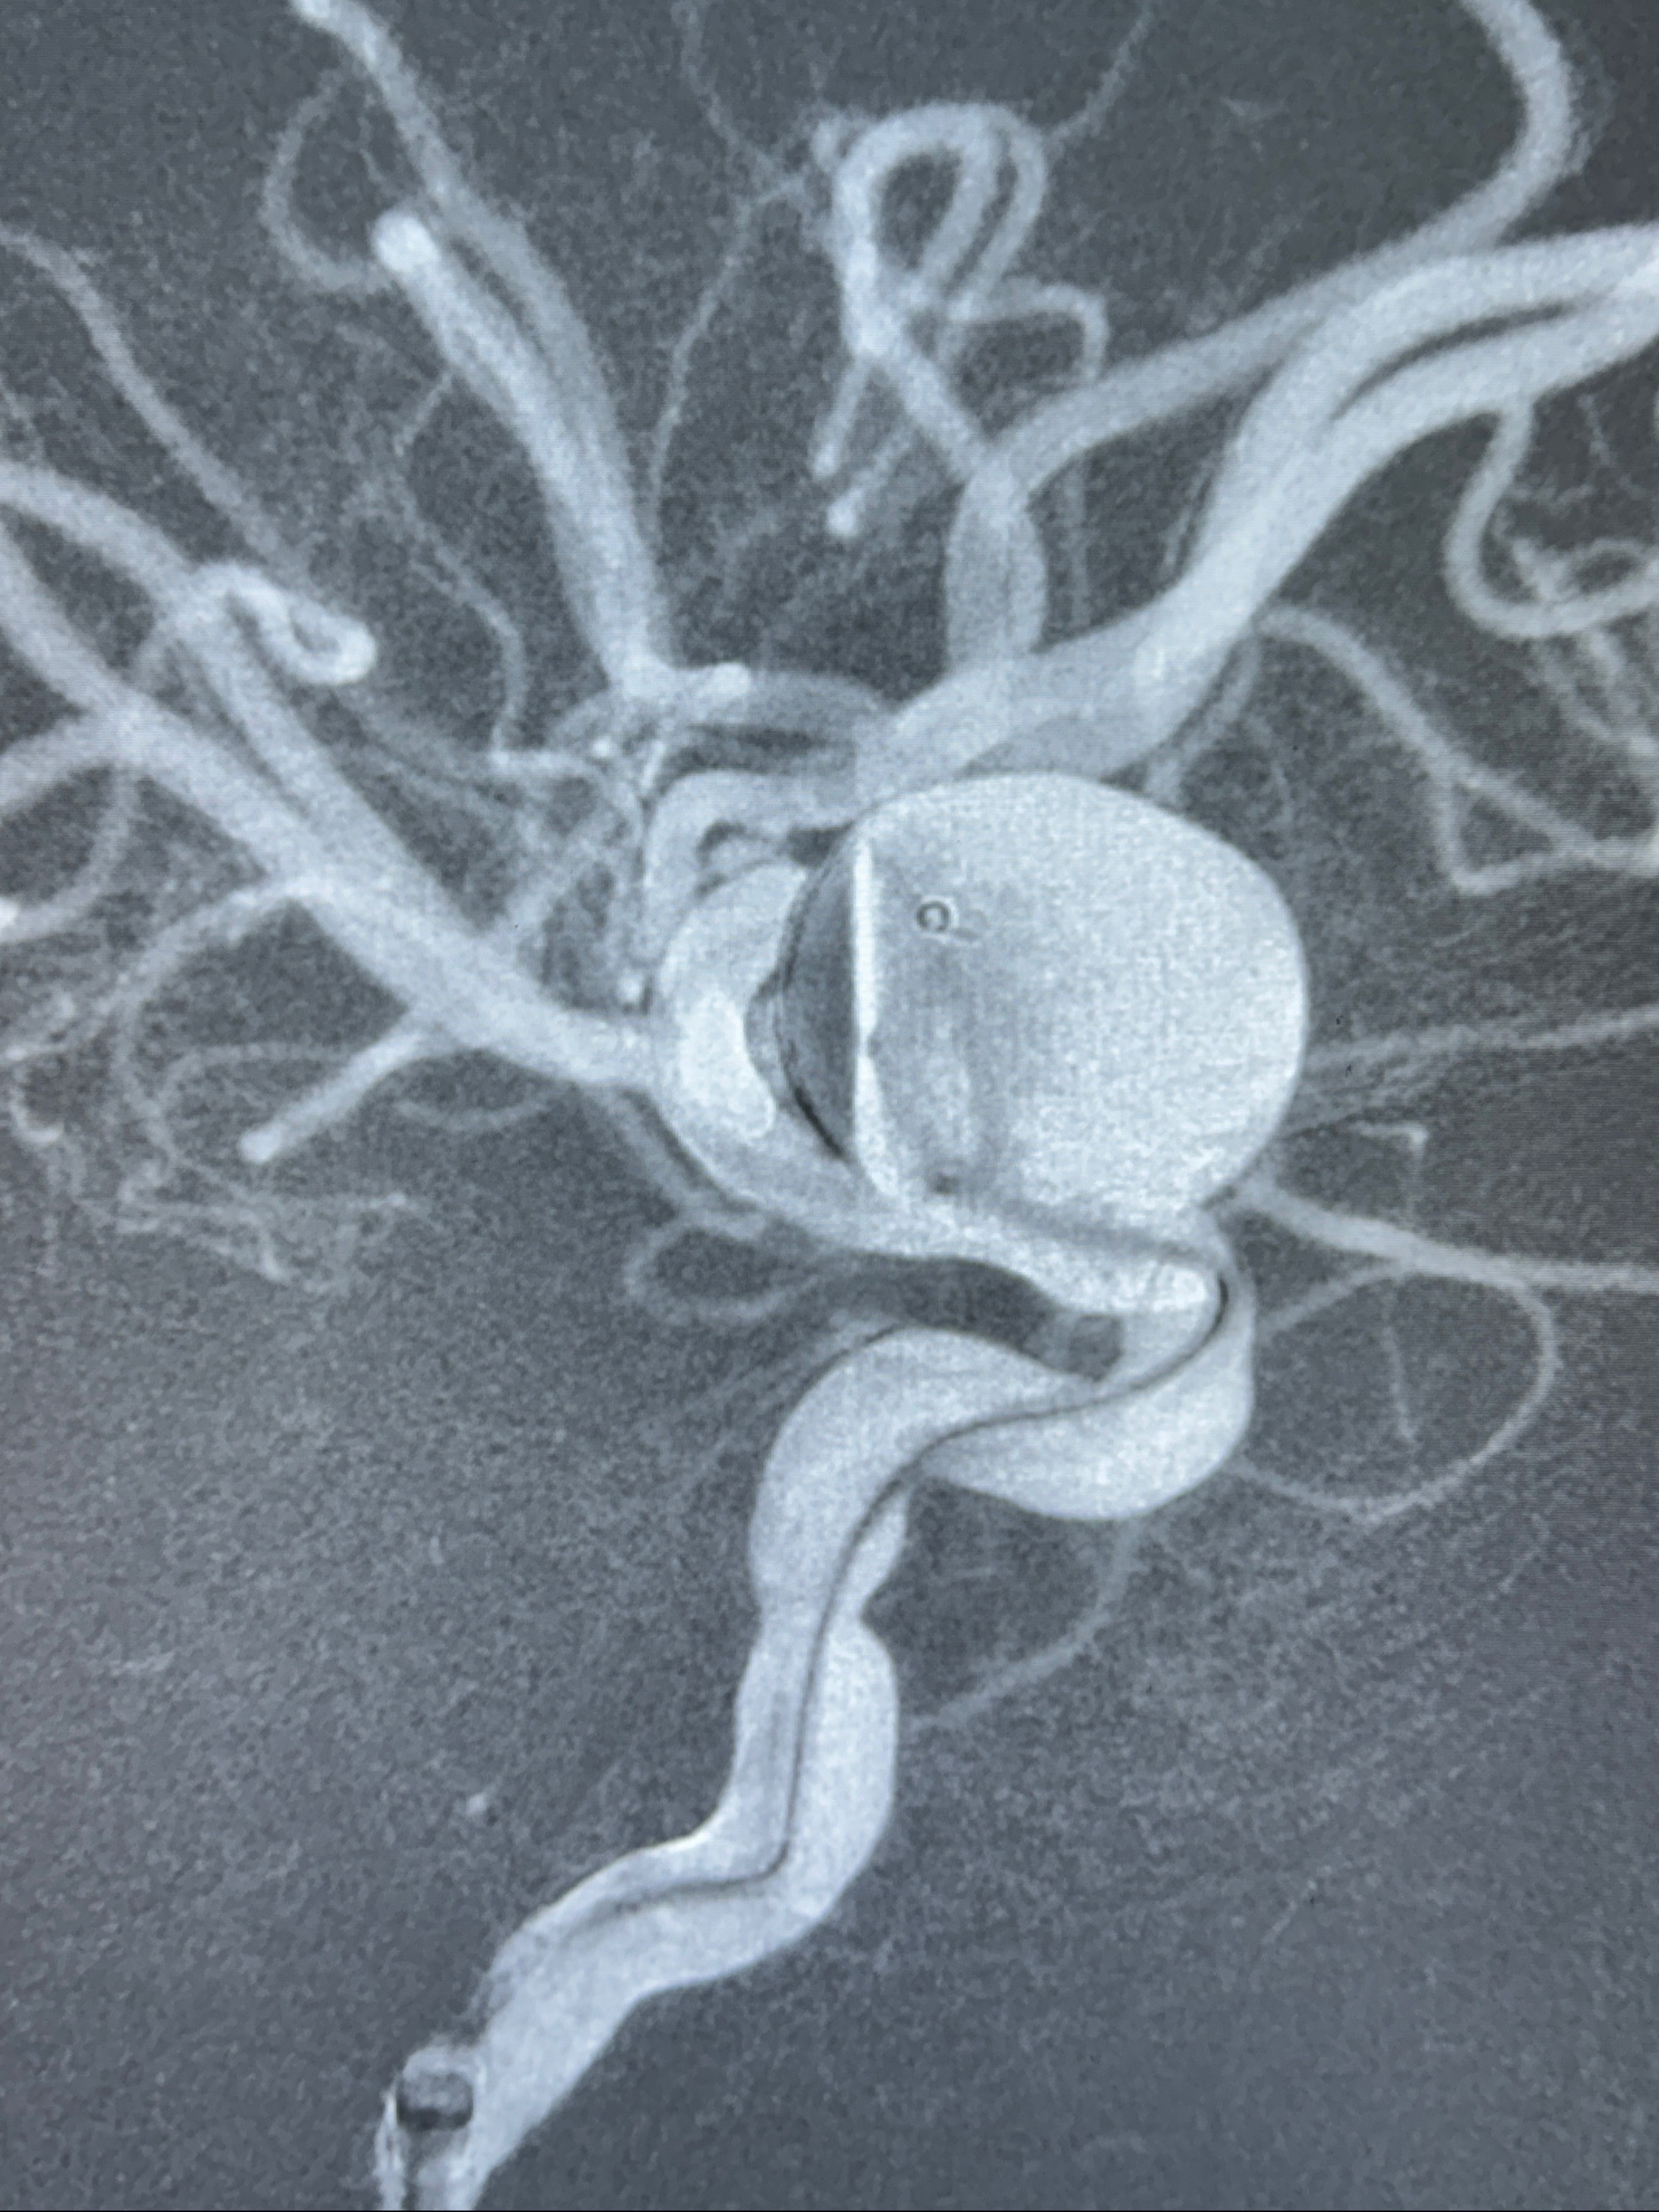

旋转3D展示动脉瘤局部的血管构筑

测量动脉瘤的大小:16*13.8*7.6mm大小,较原先变大,考虑双抗后瘤内血栓溶解可能

4.5-30mmTurbridge密网支架,于M1近心端打开

多角度显示支架打开情况

造影显示支架贴壁情况

支架植入顺利,贴壁佳,支架内血流通畅,动脉瘤内血液滞留明显